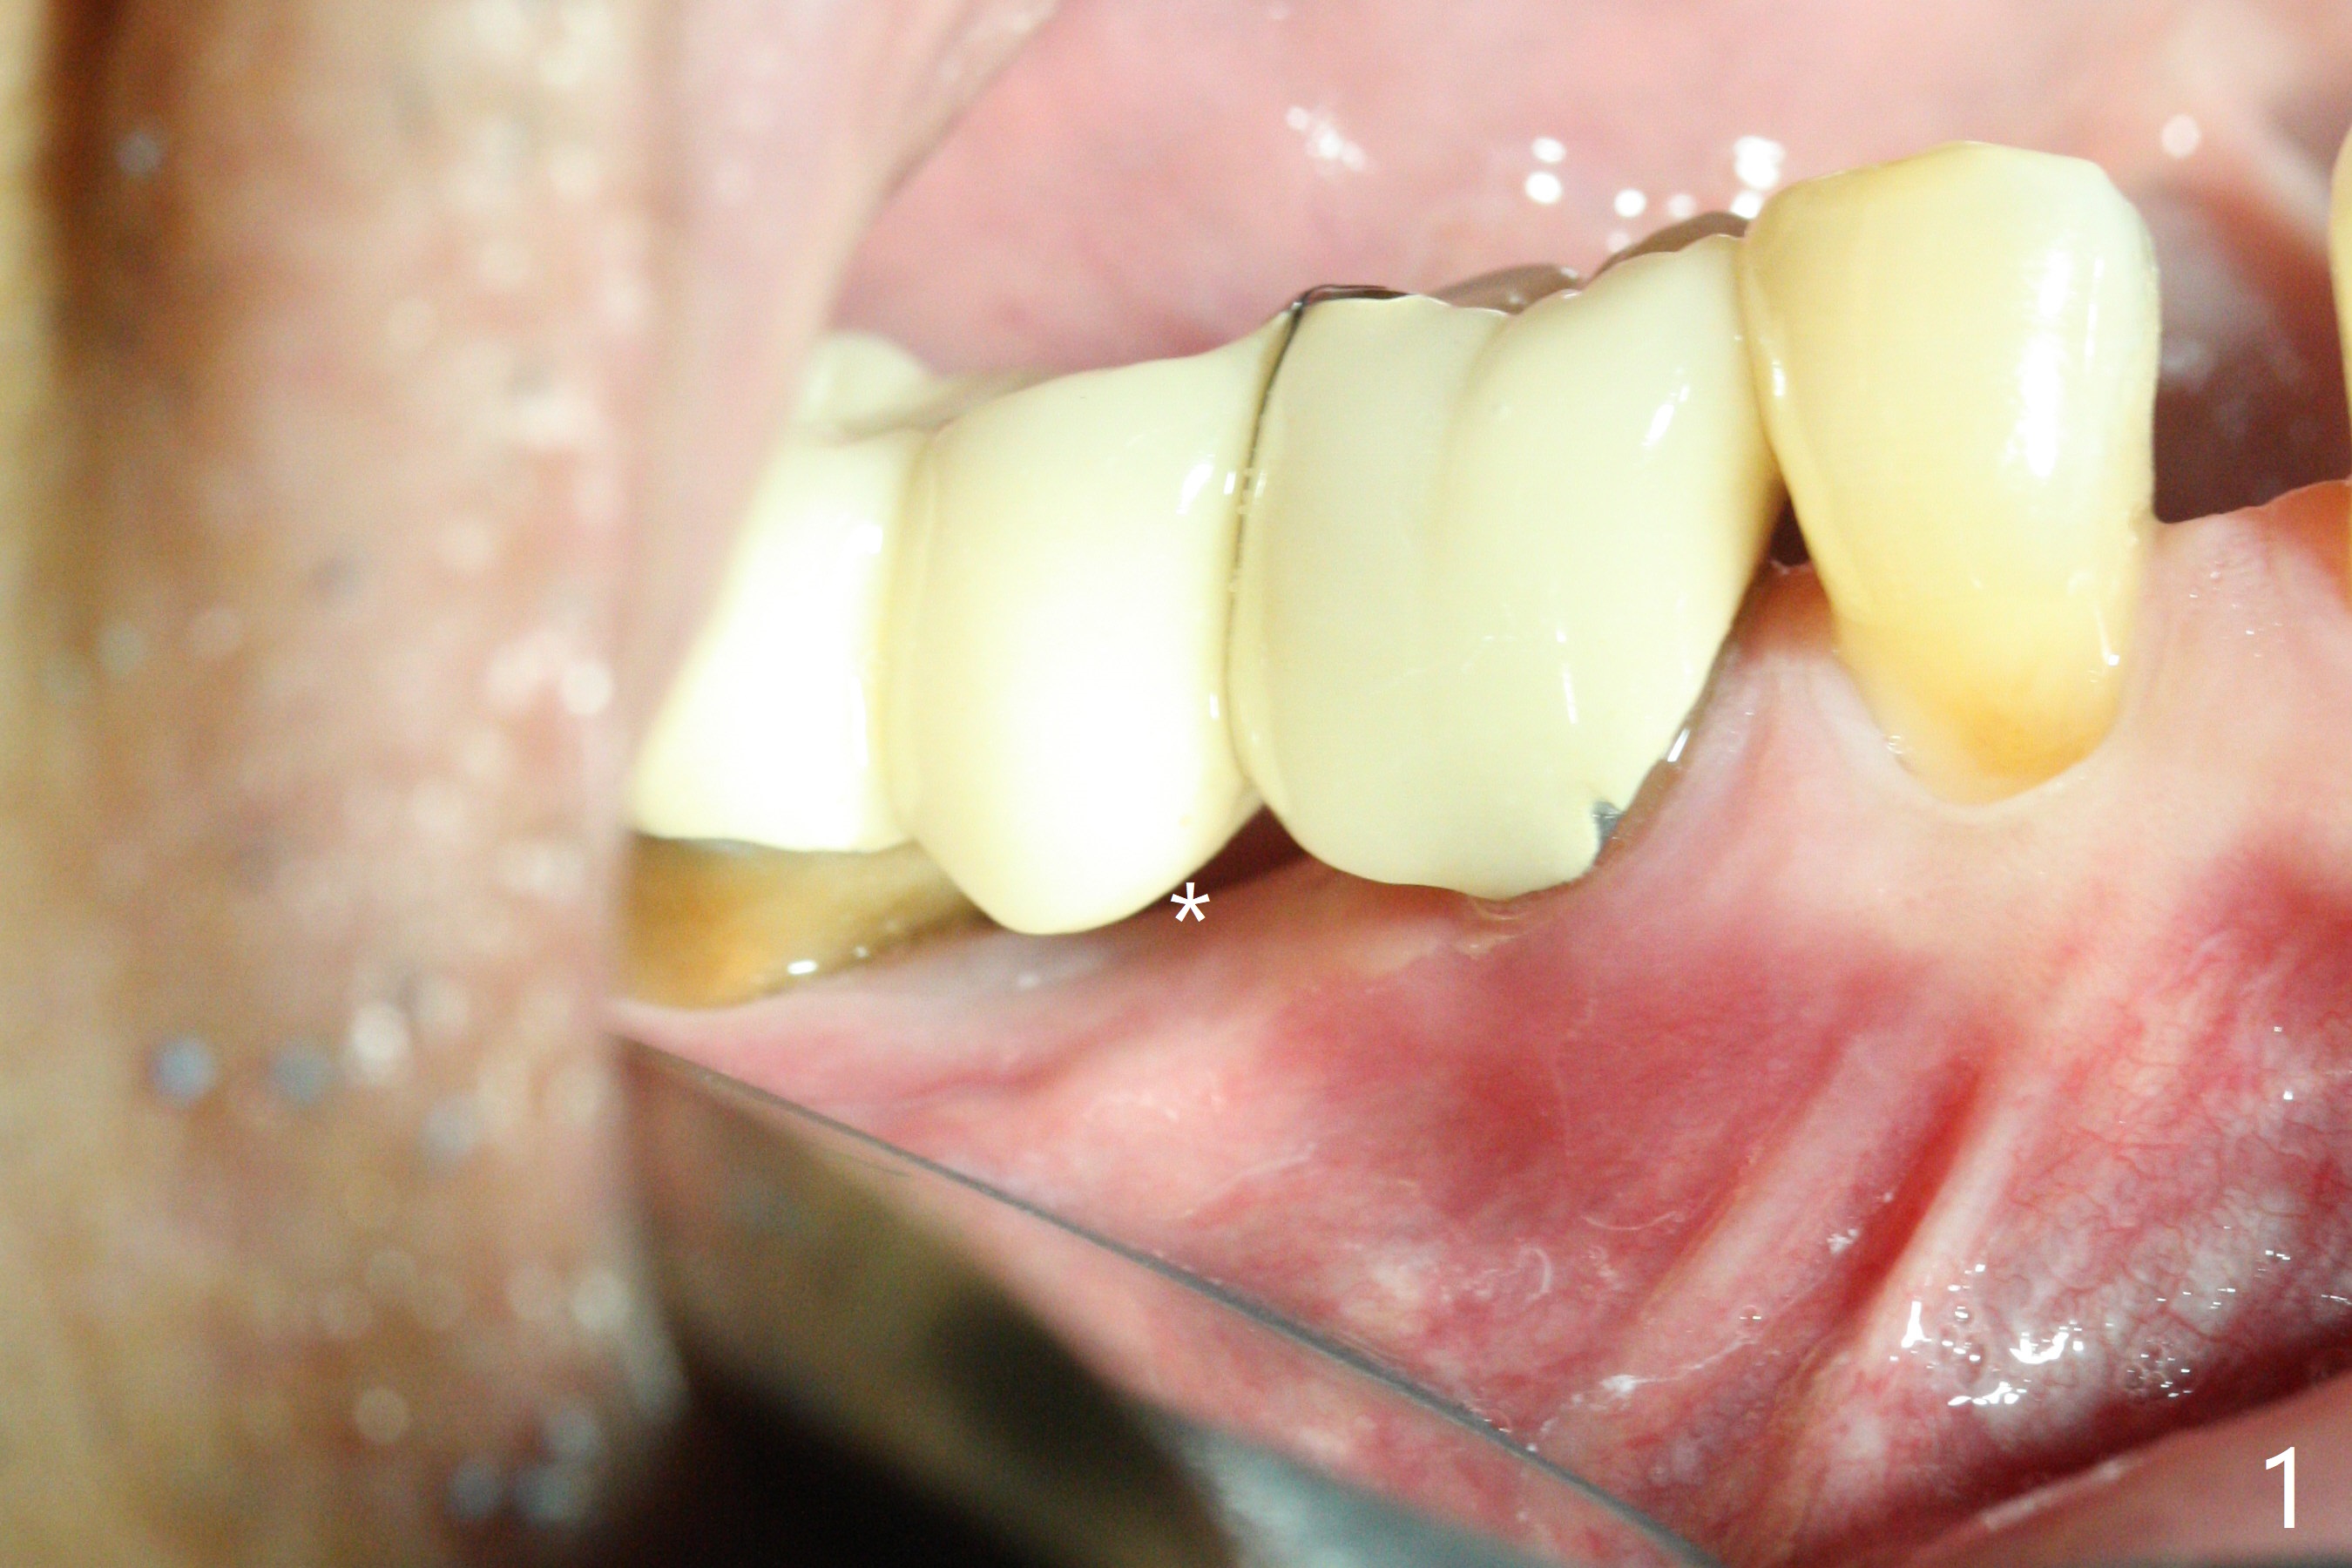

There is a space underneath the pontic at #30 (Fig.1 *), the basis for food impaction. After sectioning between the pontic and the posterior retainer, the pontic is removed from the anterior retainer with an attachment (Fig.2 *). The initial depth of osteotomy is 10 mm following ridge top reduction (Fig.3). A 3x10(4) mm 1-piece implant is placed with >50 Ncm; to reduce possibility of crown dislodgement from the implant, the retainers will be kept with modification of the proximal surfaces as shown by curved lines in Fig.4. Periodontal dressing is applied after suturing. There is no postop paresthesia. The periodontal dressing remains in place 2 weeks postop because of engagement into the attachment slot and undercuts (Fig.5). The patient returns 3 months postop; after minor contour adjustment (Fig.6 red curved line), impression is taken. The permanent crown is temporarily cemented (3.5 months postop) in case of food impaction due to the distal overhang of the tooth #29 (Fig.7). In fact the patient returns 4.5 months post cementation with right TMD (muscle relaxant prescribed) and food impaction, although there is no bone resorption (Fig.8,9). It appears that the crown at #29 needs to be redone, while porcelain will be added to the mesial surface of the one at #30 (Fig.10 red lines). In fact the crown at #30 is redone because of loose proximal contact with #31; there is no bone resorption 13 months post cementation (Fig.11). Bone resorption remains unnoticeable 28 months post cementation (Fig.12,13).